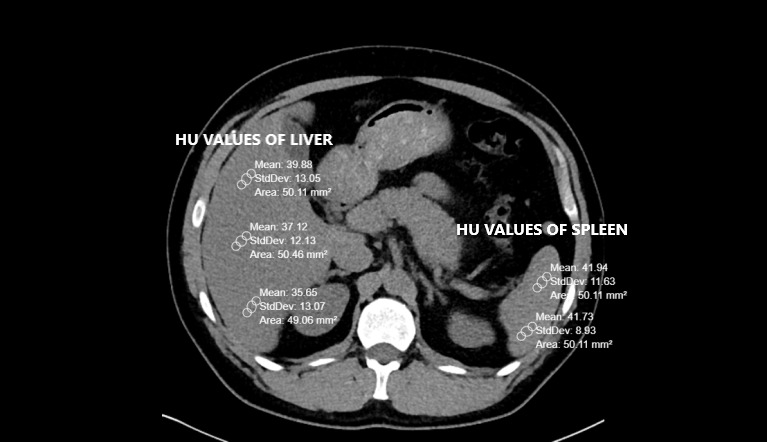

Methods: A convenience sample of 92 adult patients of which 19 (20.7%) were females and 73 (79.3%) were males, and with a mean age of 30.19 (SD = 6.00) were included. The authors calculated Hounsfield Units (HU) (i.e., relative quantitative measurement of radio density) of patients' livers and spleens on non-contrast computed tomography (CT). Liver and spleen differences < 10 HU were considered steatosis (FLD). The authors stratified sample patients into two analytic subgroups according to the presence of FLD or not and compared them based on their FRS widths.

Results: In the FLD subgroup (N = 48), the difference of HU values between liver and spleen was -5.19 (SD = 11.32), with a range of -38 - 8 HU, while, in the non-steatosis subgroup (N = 44), the mean difference was 16.36 (SD = 3.90), range of 11 - 26 HU. The average diameter of FRS width was 12.5 mm in those patients with steatosis (FLD subgroup) although 9.3 mm in non-FLD patients. (p = 0.02).